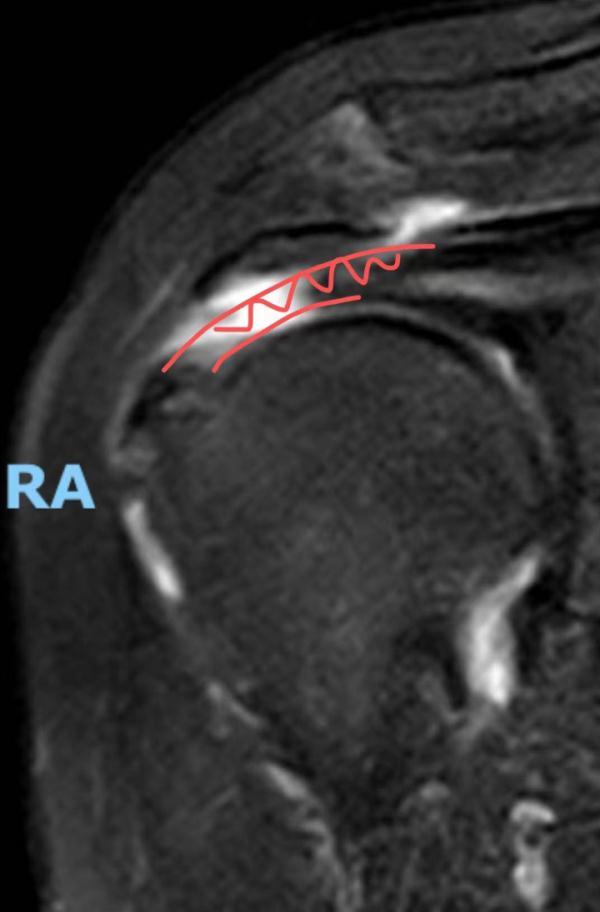

在磁共振的火眼金睛之下,所谓的“肩周炎”原形毕露——吴阿姨患上的根本不是肩周炎,而是严重的肩袖撕裂。

(白色区域显示肌腱断裂)

简单来说,吴阿姨肩膀的疼痛是因为肩关节里面的肌腱断了,而之后的用力锻炼使得肌腱断裂更加严重。田飞通过一台微创肩关节手术为吴阿姨缝上了撕裂的肩袖:使用特制的锚钉和超强缝线,将断裂的肌腱拉回原位缝合并加固。手术顺利。